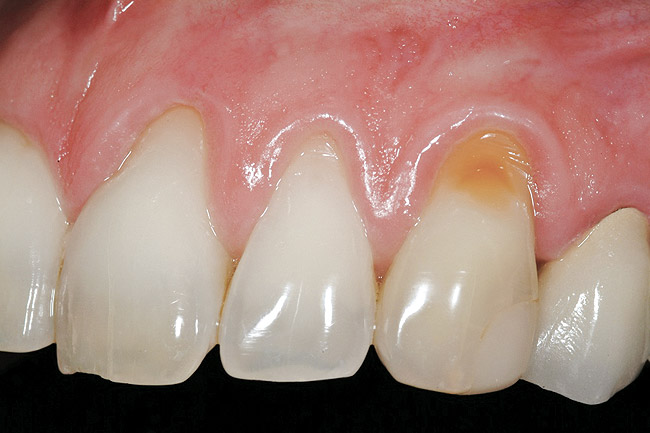

Figure 20 shows the completed view with the final restoration seated. Observe the balance of the facial heights of contour between the central incisors, and the presence of a thick-biotype, attached keratinized tissue.

Figure 20  Case Two Case Two, complete view.

Figure 20